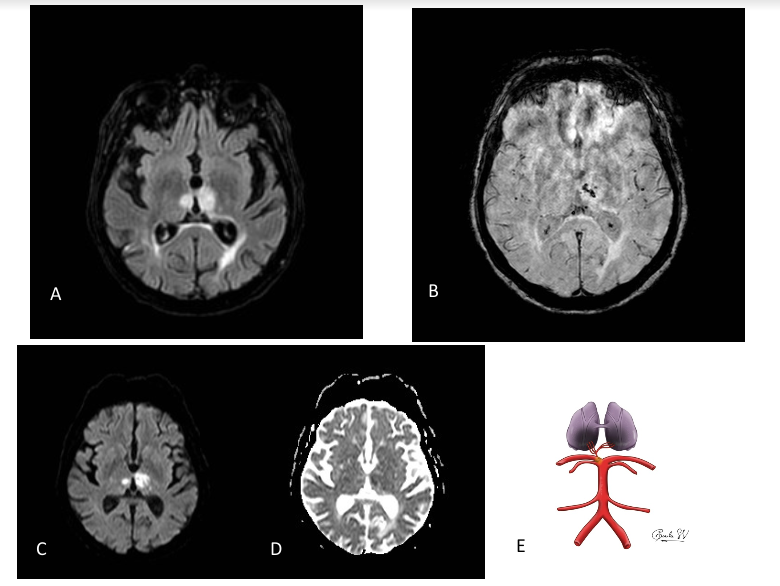

A: Secuencia FLAIR axial, donde existe hiperintensidad de señal de la superficie medial de ambos tálamos.

B: Secuencia de susceptibilidad magnética axial, con presencia de microhemorragias puntiformes en el tálamo izquierdo.

C Y D: Secuencias axiales de difusión b=1000 (C) y mapa de ADC (D), donde se observa restricción de la difusión.

E: Esquema de una posible variante anatómica de la irrigación del tálamo.

En las imágenes de RM se muestran hallazgos compatibles con infartos isquémicos agudos en la región medial de ambos tálamos, con transformación hemorrágica petequial.

Al tratarse de infartos en territorios bilaterales se plantea como primera posibilidad un síndrome de Percheron, manifestándose como un ictus cardioembólico secundario a la fibrilación auricular no anticoagulada que presentaba la paciente, lo que explicaría la afectación sincrónica de ambos territorios vasculares.

El síndrome de Percheron consiste en un infarto talámico bilateral por obstrucción de la arteria de Percherón, variante anatómica de la vascularización del territorio posterior (presente en el 4-12% de la población), donde la irrigación de los dos tálamos proviene de la misma arteria cerebral posterior de forma unilateral.